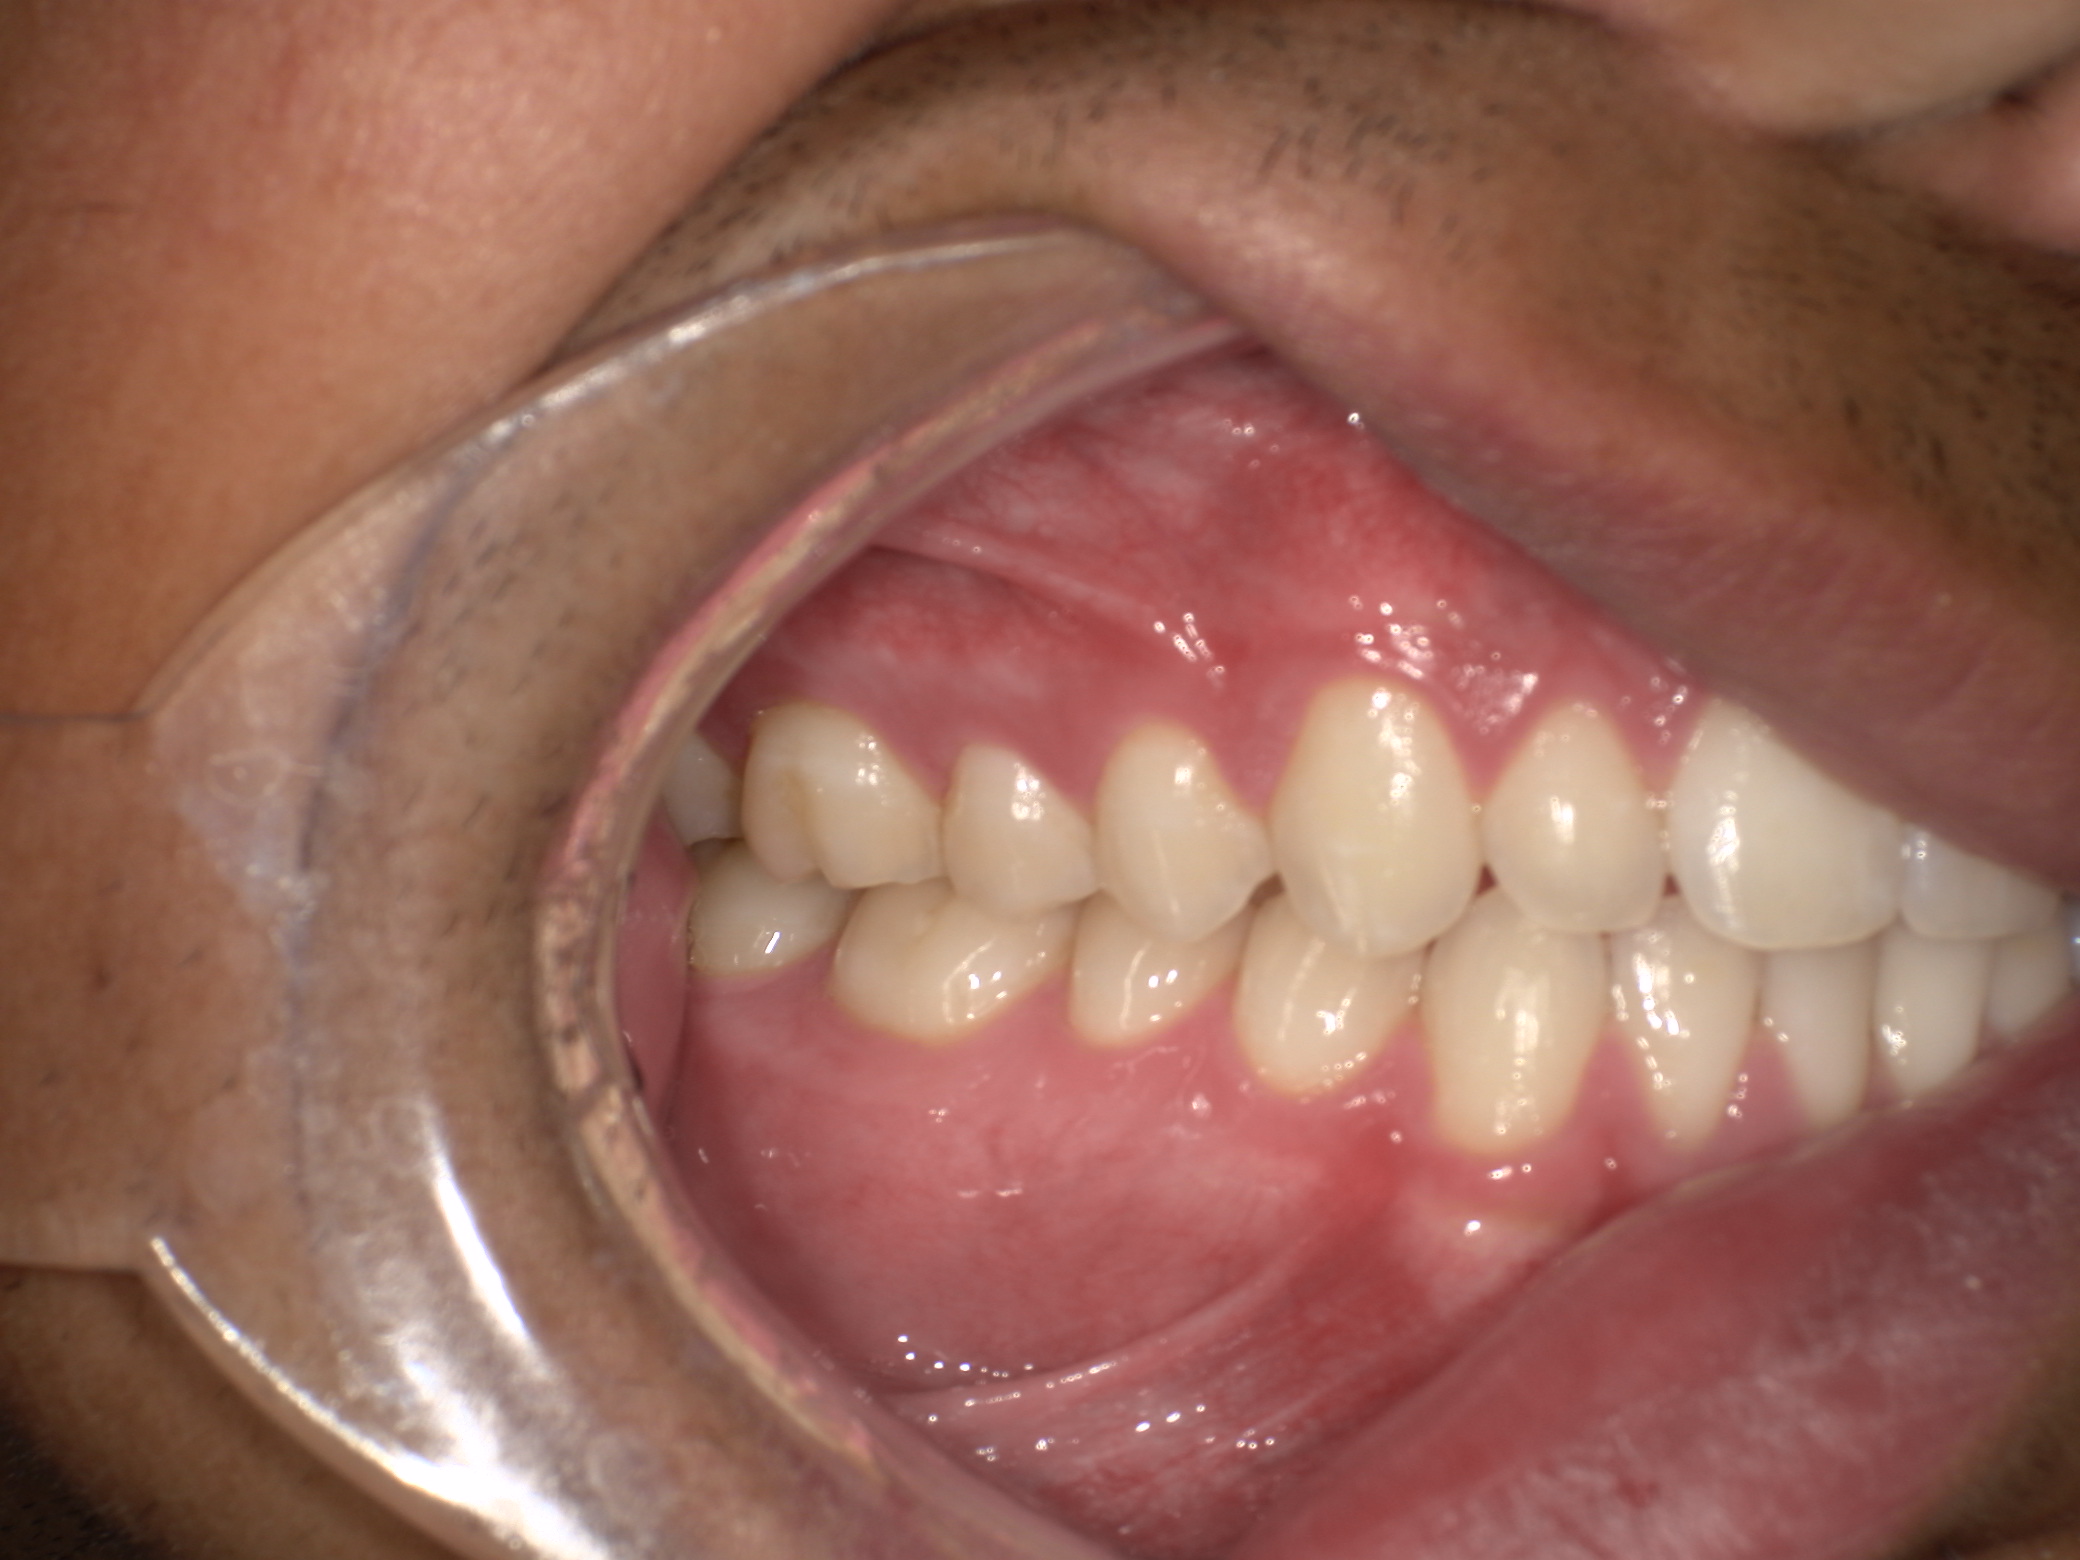

Your evaluation includes a CT scan, comprehensive oral images, sleep assessment, and personalized treatment plan from Dr. Trivedi. If you choose to proceed with the complete solution stack, your evaluation costs will be applied as a discount.

After your evaluation, the doctor reviews your results and explains how your airway structures are impacting your health. You’ll then receive a personalized plan that may include palatal expansion, aligners, or other therapies to optimize your health.